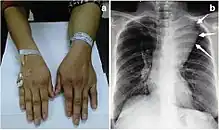

| Large mediastinal angiolipoma | |